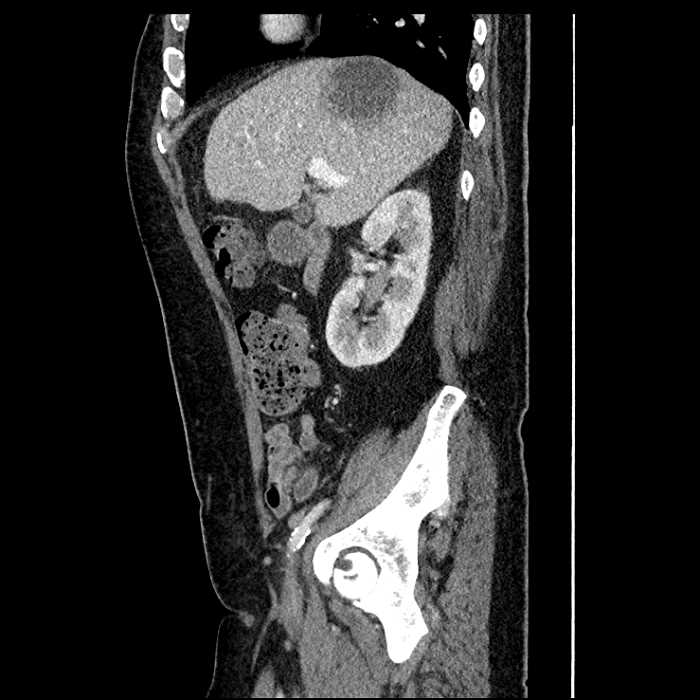

• Large fluid density structure in hepatic segments 7 and 8 measuring 10 x 7 x 7 cm with internal septation and circumferential ill-defined low density compatible with edema

• Peripherally enhancing subcapsular collections along the anterior margin of the left hepatic lobe measuring 3 x 1 cm and 2 x 1 cm

Acute sigmoid diverticulitis complicated by a small contained perforation and a large abscess in the right hepatic lobe. Additional small subcapsular abscesses along the anterior margin of the left hepatic lobe.

• The classic CT imaging appearance is a double target sign with internal low density surrounded by an internal enhancing rim (capsule) and a low density external rim (edema)

Hepatic abscess showing the double target sign with low density internally surrounded by a thin inner enhancing rim (red arrow) and ill-defined outer low density rim (yellow arrow). Blue arrow indicates an internal septation. Red arrows: additional smaller subcapsular abscesses. Red arrow: focal contained perforation associated with diverticulitis.